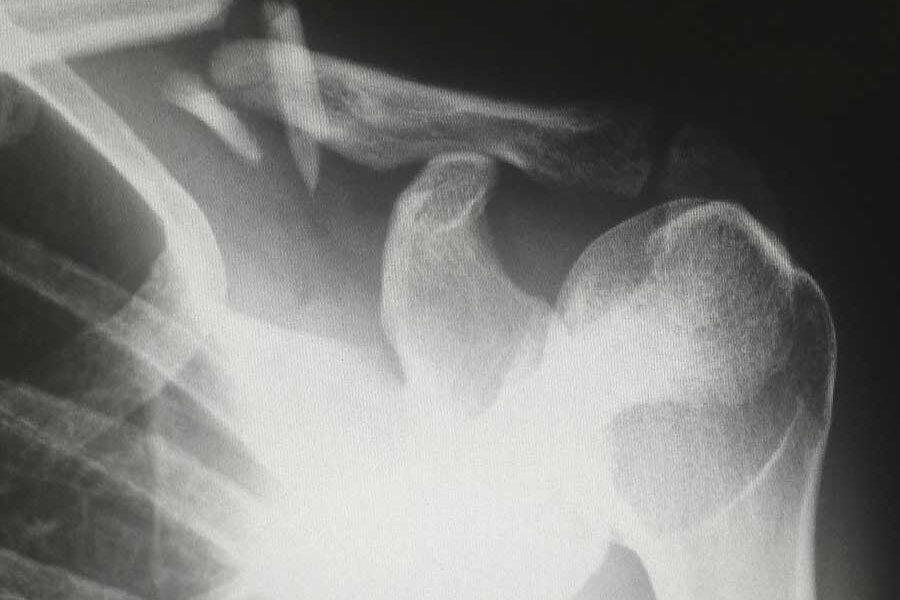

Dolore spalla: frattura della spalla. La spalla è la seconda articolazione come incidenza specialmente nelle persone anziane a fratturarsi spesso per motivi di osteoporosi.

Diagnosi: esame radiografico in due proiezioni se eseguibile ed esame TC della spalla con ricostruzione 3D

Trattamento: se la frattura è composta, cioè se non c’è una dislocazione importante dei frammenti si può proporre il trattamento conservativo specialmente se le condizioni generali non lo permettono.

Se la frattura ha almeno tre frammenti, se il paziente è giovane, se il paziente è anziano ma attivo, se la frattura ha il frammento articolare schiacciato in varo (alto rischio di necrosi della testa dell’omero) si procede per l’intervento chirurgico.

Osteosintesi: la sintesi della frattura può avvenire con una placca se i frammenti sono piccoli e lontani fra di loro oppure se sono vicino fra di loro e non sono più di tre all’incirca anche con un chiodo endomidollare che e’ un tubo che entra all’interno del canale osseo dell’omero e poi con delle viti blocca i frammenti.

Protesi: quando la frattura è troppo scomposta o i frammenti sono tanti e troppo piccoli da sintetizzare è meglio ricorrere alla protesi inversa che è un impianto che farà lavorare la spalla anche senza la cuffia dei rotatori che spesso è disinserita per la frattura